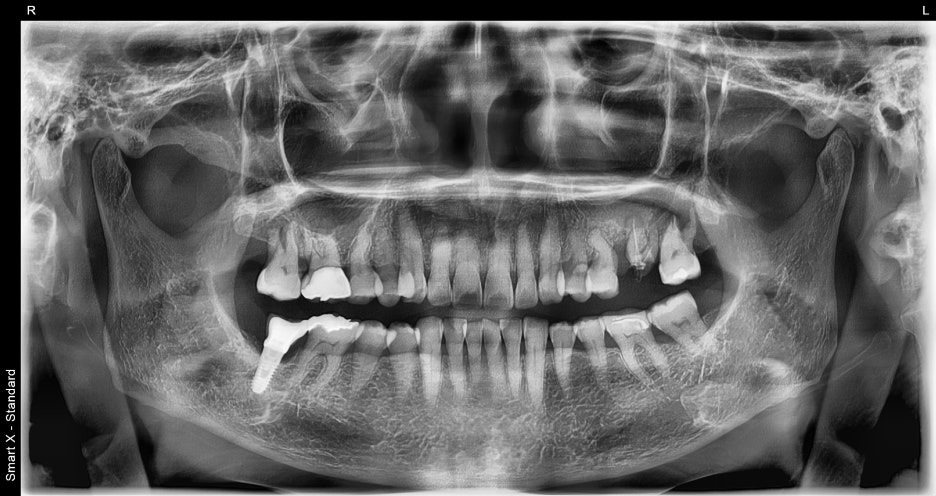

At the first visit

At Seoul Orbit Dental Hospital, we take a 3D CT scan before all implant treatments.

In this case, we found:

-

Severe bone loss around #26 and #27

The maxillary sinus had descended significantly

Inflammation between the root and the gum

Based on the panoramic X-ray and intraoral photos,

we diagnosed the following:

The two upper left molars were fractured and missing

The surrounding alveolar bone was relatively healthy, so implant placement was possible with minimal bone grafting